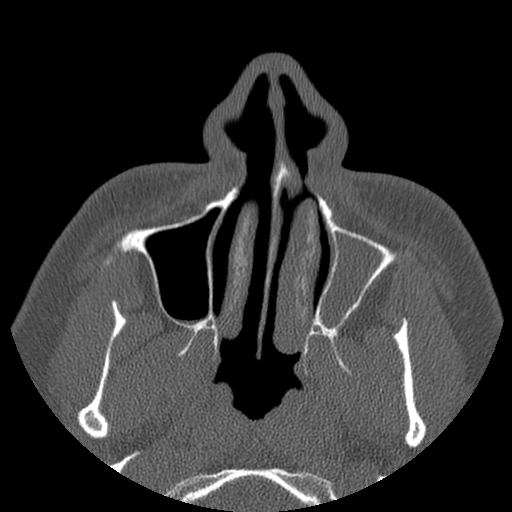

Here are a few shots illustrating how off-kilter my septum is. That line right down the middle is the septum, and it is supposed to be pretty straight. Mine, however, veers off to the left side of my body (the right in the pictures), includes a funky hook-shaped spur, and the whole nasal space is sort of off-kilter and asymmetrical. But it’s nothing that a little modern medicine can’t fix. The last picture has nothing to do with my septum, but I think it’s the coolest image on the my entire C/T scan disk.